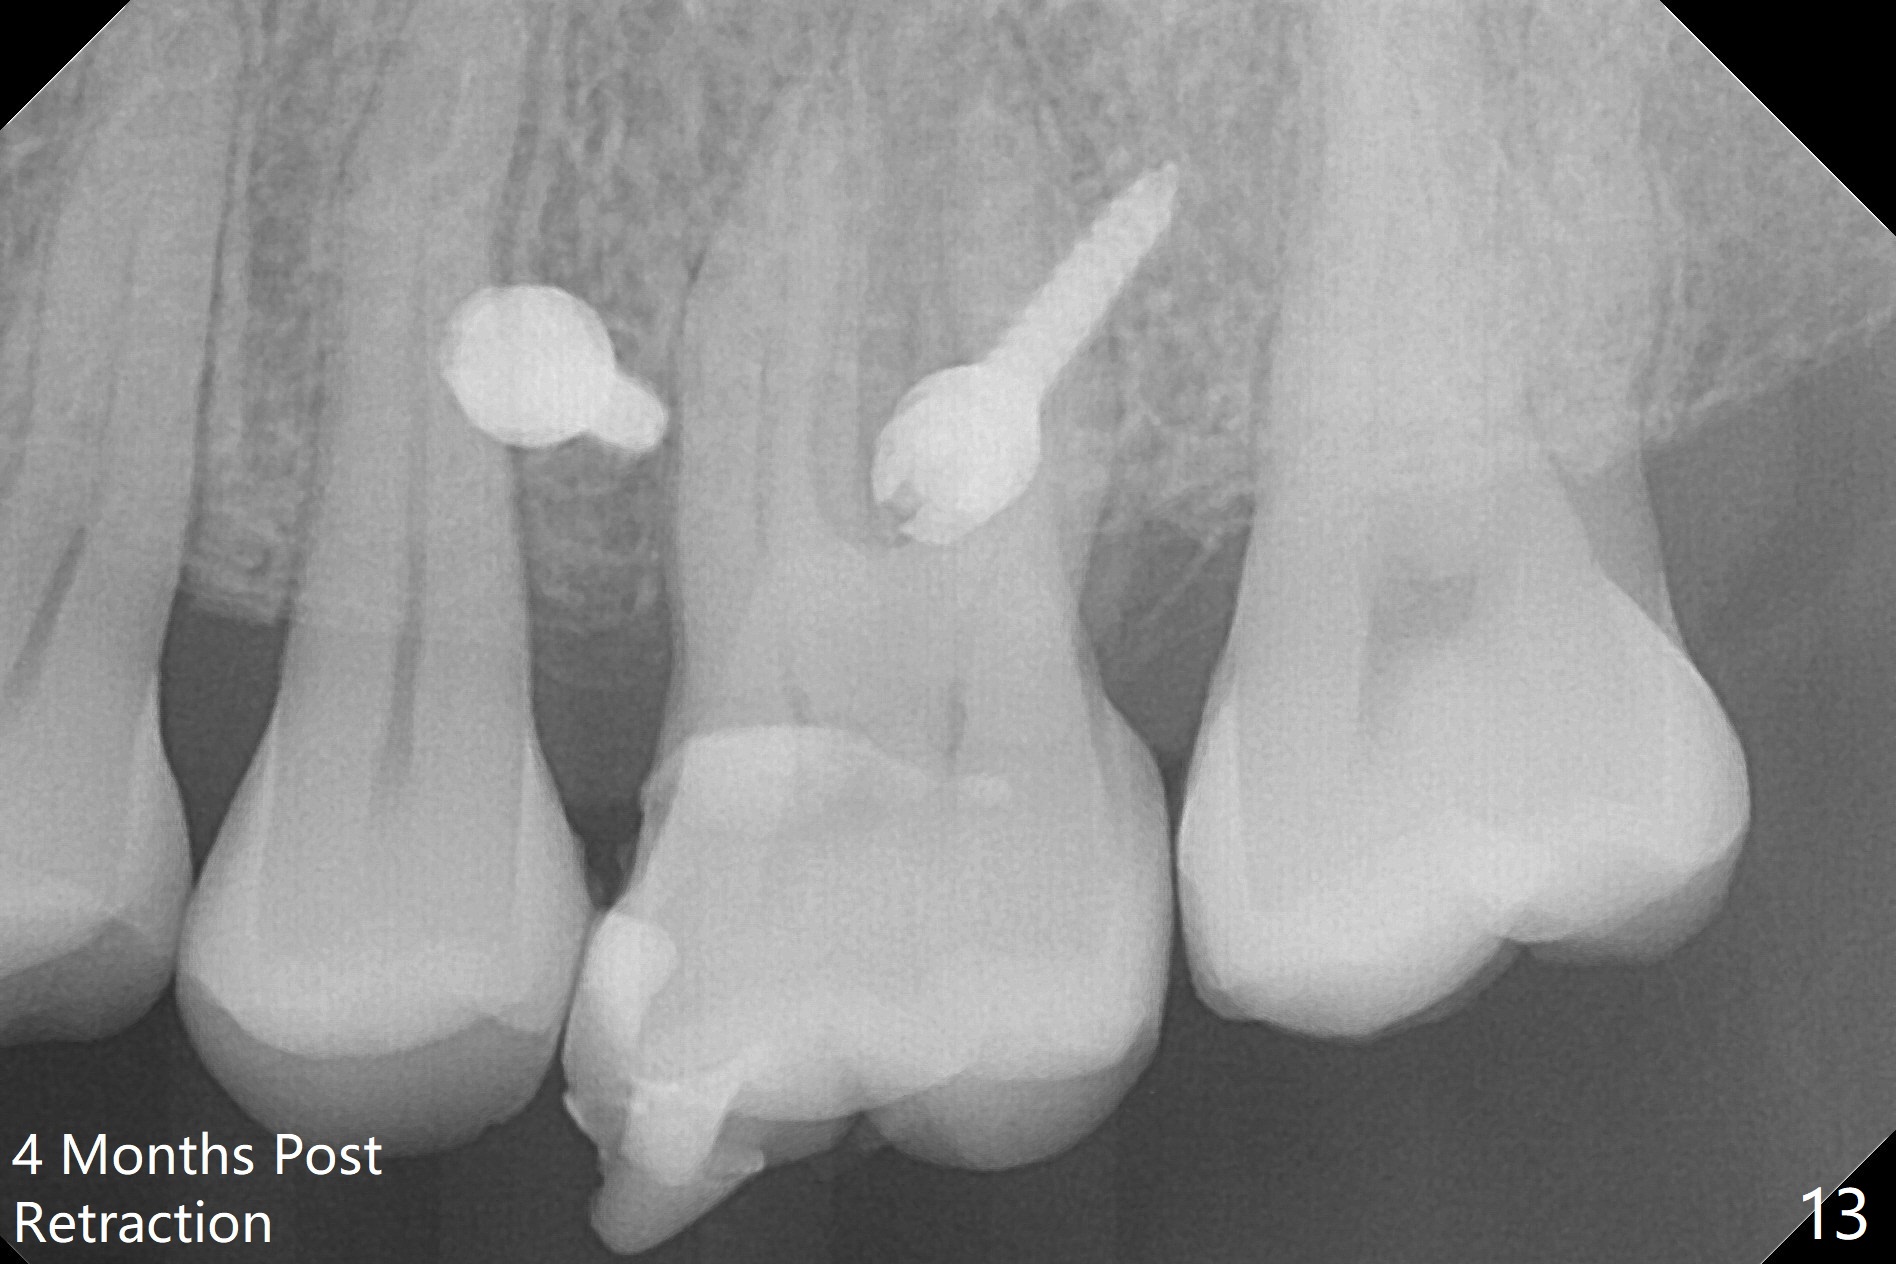

It looks as if the tooth #3 is blocked by the neighboring teeth. The proximal surfaces are reduced 1.5 months post orthodontic intrusion. Fourteen days later, the gap exists distal (Fig.10 *). It appears that the power chains placed on the natural groove of the tooth (white line) mesializes the tooth. Then the power chains are placed mesial to the mesiopalatal cusp by placing 2 of composite (Fig.11); one month later, the distal gap closes (Fig.12). The patient feels less pressure against the teeth anterior to the tooth #14. At the same time, the latter appears to have been intruded. The tooth appears to have been intruded radiographically 4 months post retraction (Fig.13).